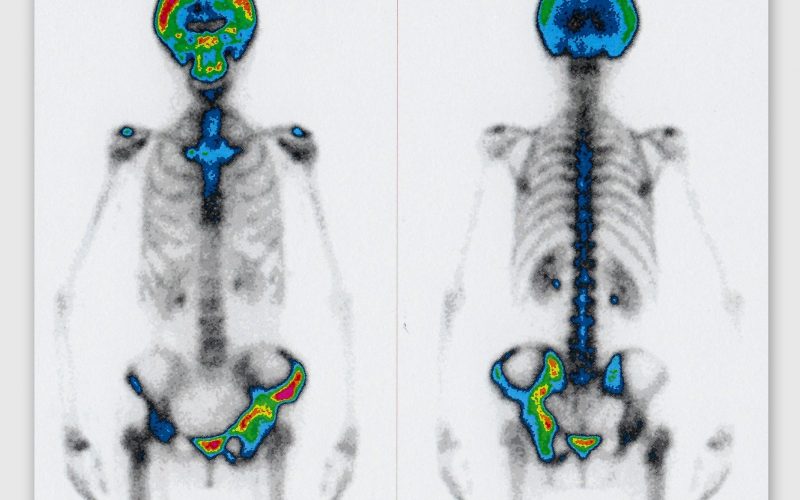

Exploración que informa de la distribución del sistema retículoendotelial de la médula ósea. Indicada para valorar la alteración de la distribución normal de la médula ósea con expansión periférica: anemia hemolítica crónica, post-QT y RT, síndromes mieloproliferativos, etc. o visualización de la distribución de la médula ósea normal de manera complementaria a la gammagrafía ósea con leucocitos marcados en el estudio de patología infecciosa ósea, especialmente en los casos de pacientes portadores de prótesis u osteosíntesis. La adquisición de las imágenes dura 20-40 minutos y se realiza al cabo de 1-2 horas de la administración del trazador.